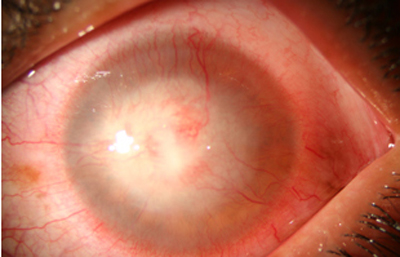

En su evolución se observará aumento del edema, agrandamiento y coalescencia de los infiltrados formando un anillo, (Figura 9, 10 y 11) que progresa hacia la formación de un absceso (Figura 12, 13 y 14), queratolisis superficial, adelgazamiento y perforación corneal (Figura 15 y 16).

Fig. 9 Síntomas de 15 días evolución

Fig. 10 Síntomas de 15 días evolución

Fig. 11 Síntomas de 15 días evolución